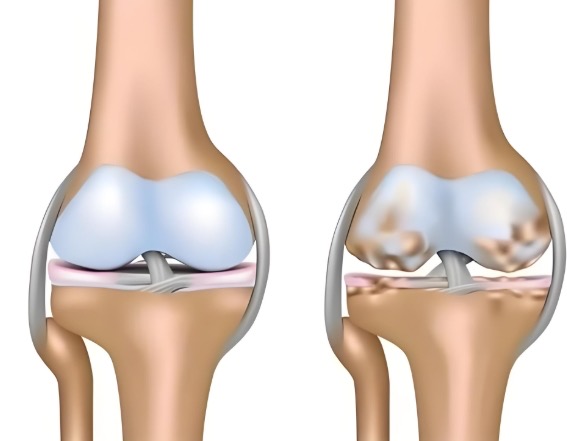

盐酸和硫酸氨基葡萄糖胶囊都是氨基葡萄糖类药物,能为关节软骨提供合成原料,在促进软骨基质的修复与再生的基础上,补充关节滑液以减少摩擦,同时通过抑制关节腔内的炎症因子,从多个方面帮助延缓骨关节炎的进展[1],但它们在临床疗效上却存在一定差异。

根据国际医学四大期刊之一《美国医学会杂志》上发布的一项研究表明,硫酸氨基葡萄糖在缓解膝骨关节炎疼痛、改善关节活动功能方面,效果优于盐酸氨糖等33种骨关节炎常用药[2]。还有相关研究显示,硫酸氨基葡萄糖不仅能延缓关节间隙变窄,还能从根源改善关节结构、减缓磨损。而盐酸氨基葡萄糖在这一关键指标上的效果尚未明确。因此,在关节保护的“确切性”上,硫酸氨基葡萄糖显然更具优势。

硫酸氨基葡萄糖胶囊中含有的硫酸根是人体关节软骨中蛋白聚糖的天然组成成分。这种与人体兼容的“内源性”特质,让它口服后吸收利用率可达90%[3]。而且对胃肠道会更温和,耐受性更佳。反观盐酸氨基葡萄糖胶囊,它所含的氯离子不是关节正常代谢所需,可能会在口服后刺激胃肠道黏膜[4]。这种刺激不仅会引起肠道不适,还会干扰药物在肠道的吸收,降低其生物利用度。